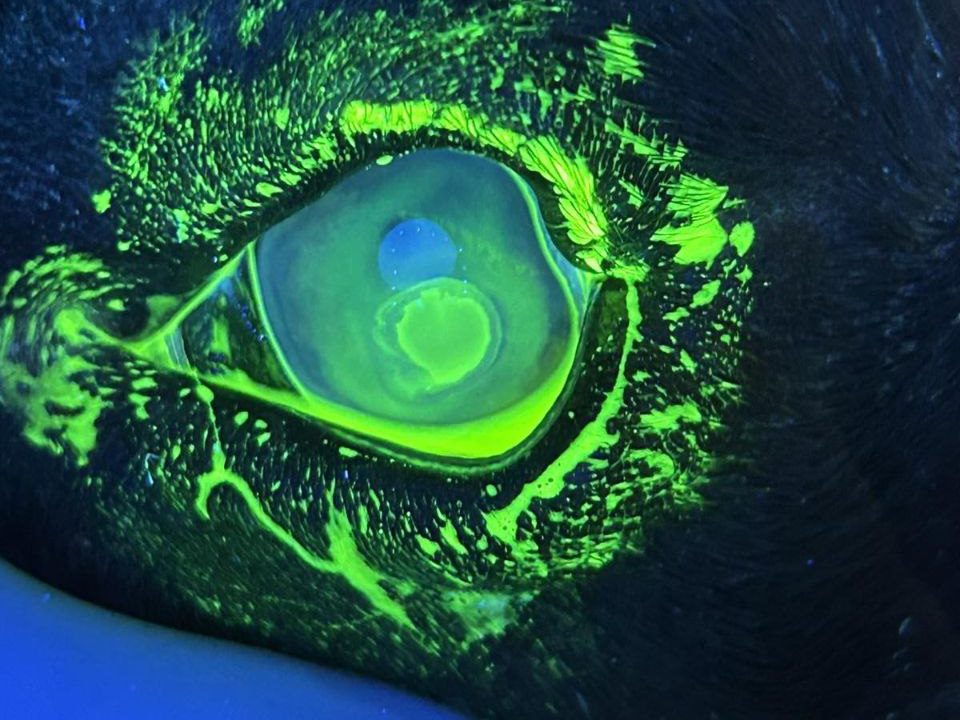

- При окрашивании флюоресциином, краситель подтекает под верхний слой роговицы как на фото выше.